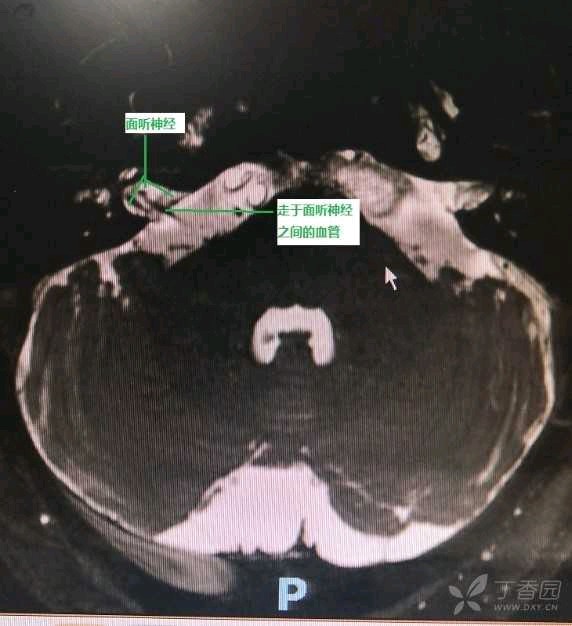

MRI提示右侧小脑前下动脉与右侧面听神经伴行

手术所见:小脑前下动脉行走于面听神经之间并对听神经形成压迫。手术将血管移开或在听神经与血管之间植入薄层垫片。术后一个月耳鸣基本消失。

术中所见:右侧小脑前下动脉行走于右侧面听神经之间,并对听神经形成压迫